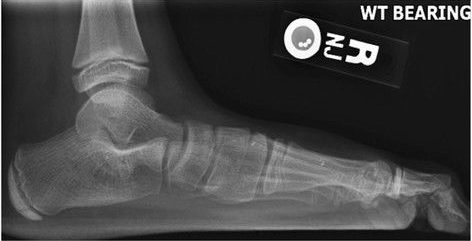

Lateral X-ray of a flat foot with C-sign, which is a bony bridge between the talar dome and sustentaculum tali, in combination with a prominent inferior border of the sustentaculum tali. This represents a talocalcaneal coalition, which is an abnormal connection between the talus and calcaneus, and is thought to cause the flat foot deformity in this case.[5]

Weight-bearing lateral X-ray showing the measurement of calcaneal pitch, which is an angle of the calcaneus and the inferior aspect of the foot, with different sources giving different reference points.[12] A calcaneal pitch of less than 17° or 18° indicates flat feet.[10]